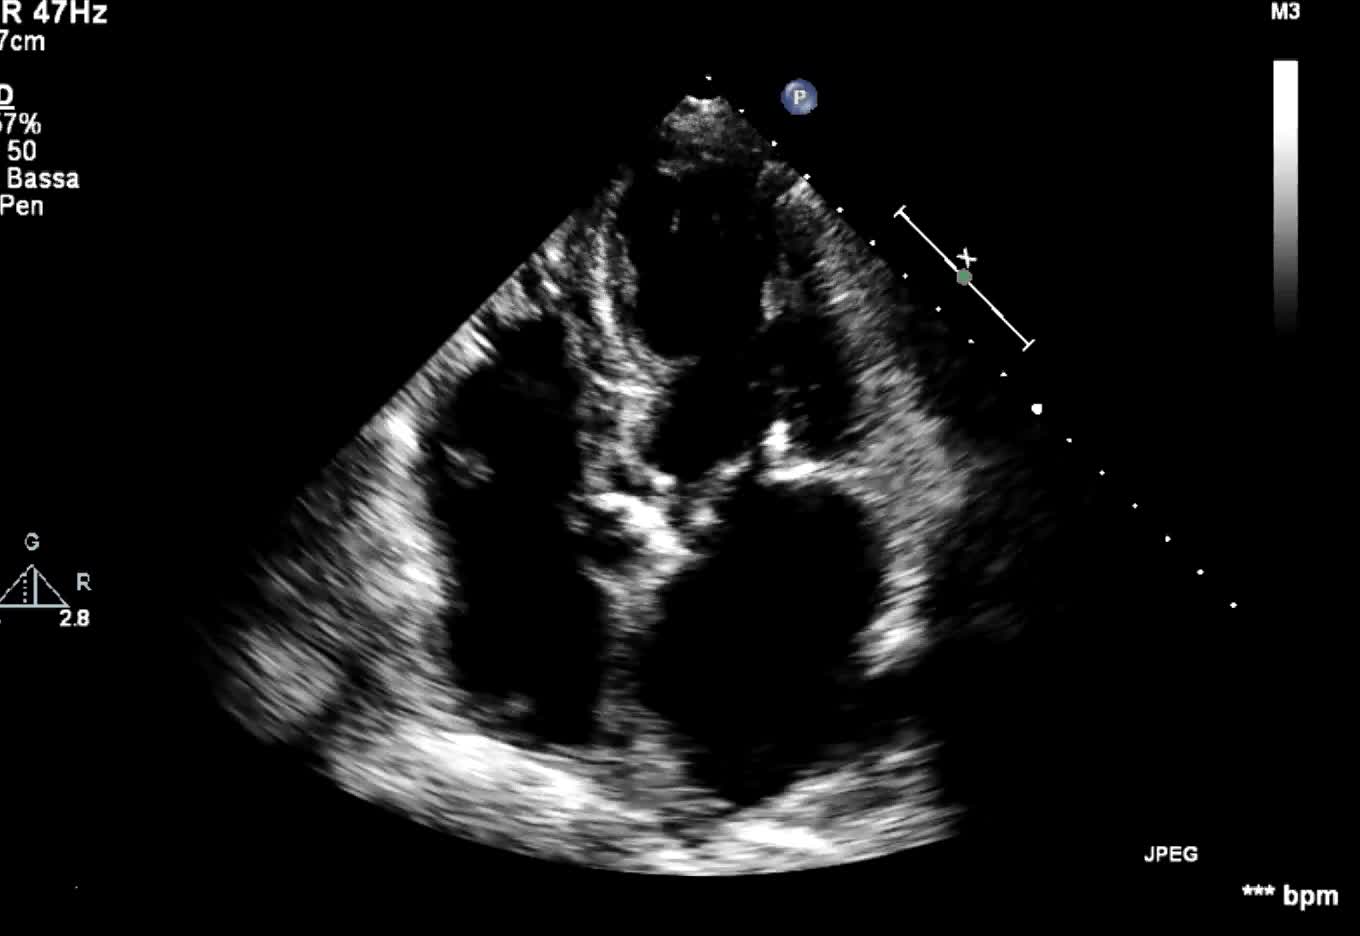

Endocardite infettiva della valvola tricuspide

Autore:

Andrea Barbieri